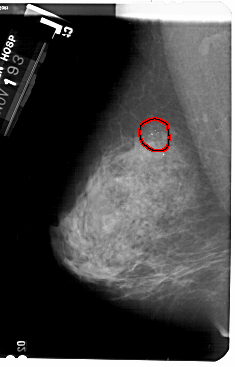

A_1732_1.LEFT_MLO

FILE: A_1732_1.LEFT_MLO.OVERLAY

TOTAL_ABNORMALITIES 1

ABNORMALITY 1

LESION_TYPE CALCIFICATION TYPE AMORPHOUS DISTRIBUTION CLUSTERED

ASSESSMENT 2

SUBTLETY 4

PATHOLOGY BENIGN

TOTAL_OUTLINES 1

BOUNDARY